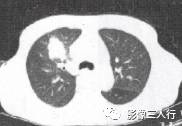

由于实变的肺组织与含气的支气管相衬托,在实变区中可见透明的支气管影即空气 支气管征,临床常见于大叶性肺炎的实变期,包括红色肝样变及灰色肝样变期,表现为密度均匀的致密影内可见透明的支气管影(图1)。这一征象被认为是肺泡炎性病变的有力证据。 医学百科网 | YxBaike.Com